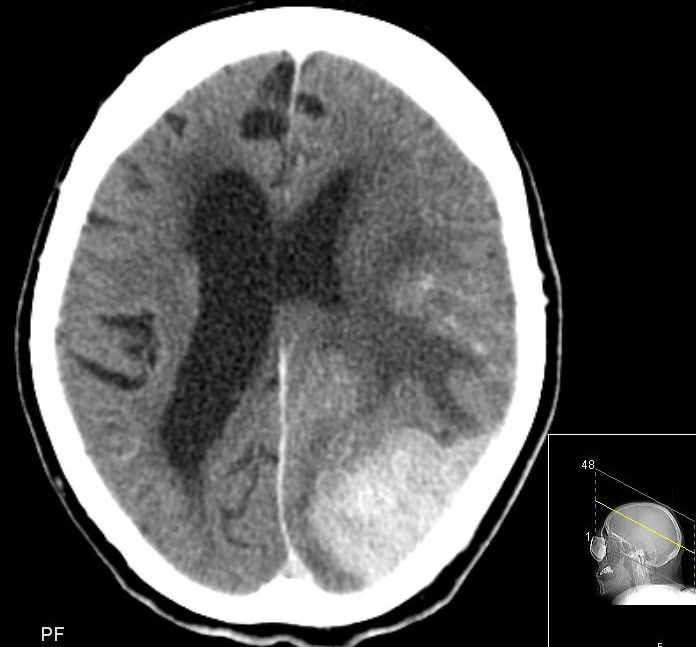

| CT | 76-jährige Frau, die vor fünf Jahren ein 8 mm großes, Tripel-negatives Mammakarzinom hatte. Nach einem Sturz im Heim wurde ein CT angefertigt. Die Bilder zeigen eine Metastase der Schädelkalotte und einen großen intrazerebralen Tumoranteil mit Kompression des linken Hinterhorns. | ||||||||||||||||||||||||||

![]() |

![]() | ||||||||||||||||||||||||||